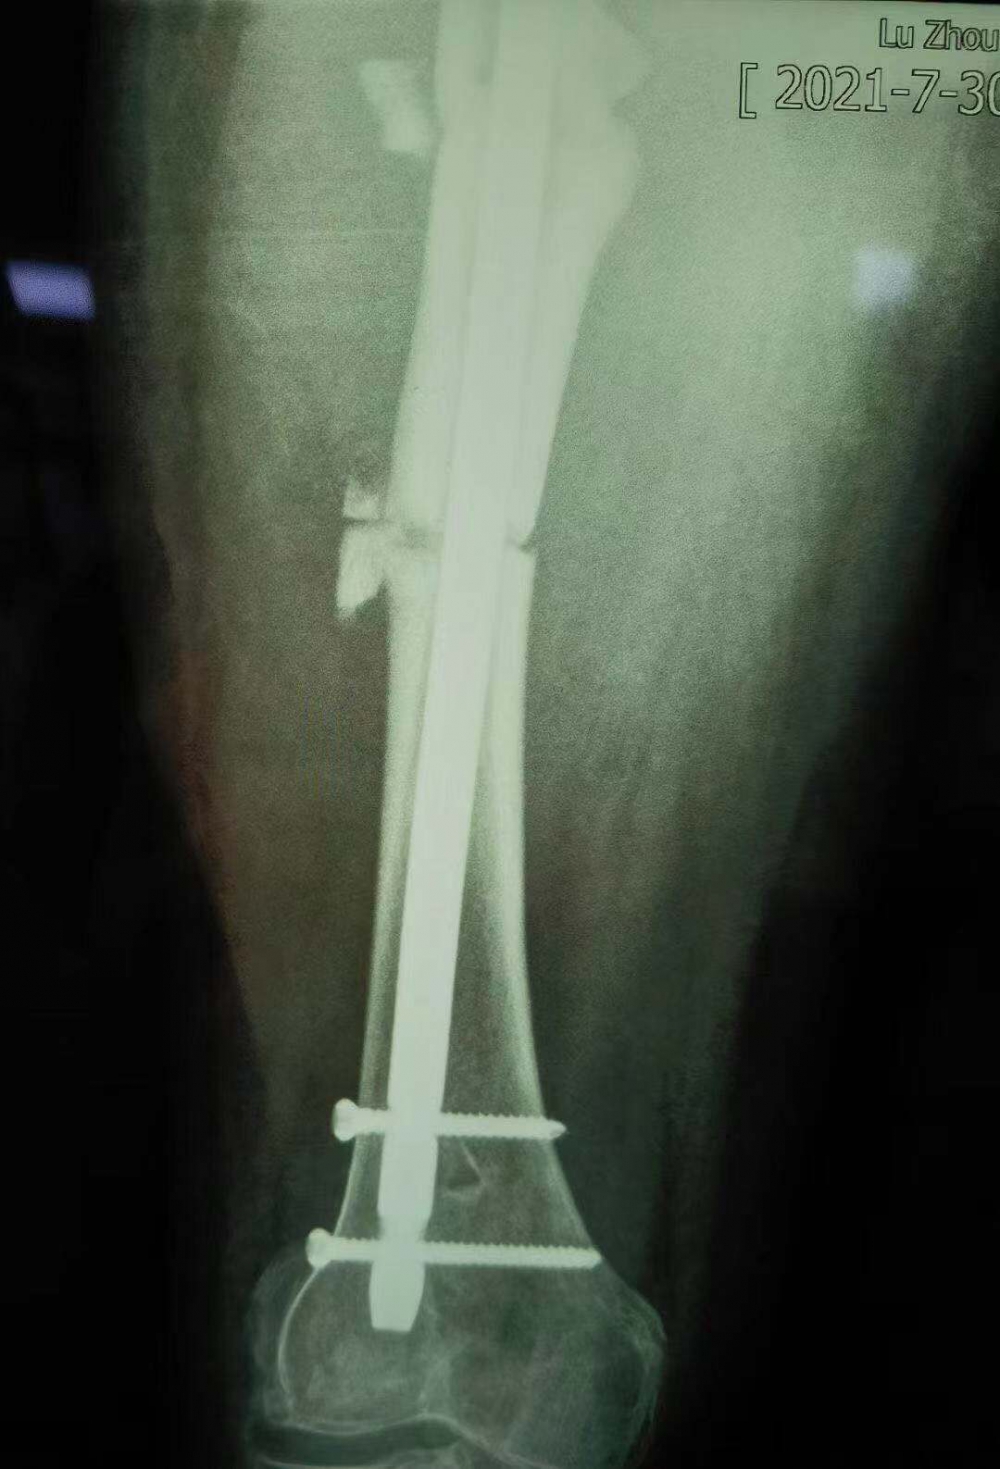

術后拍攝的X光片

但因張女士屬于股骨上段骨折畸形以后手術歸正,整個股骨頭的負重區(qū)已經(jīng)發(fā)生了一些改變,髖關節(jié)關節(jié)炎也可能存在,因此張女士還需進行后續(xù)的康復性治療和護理。